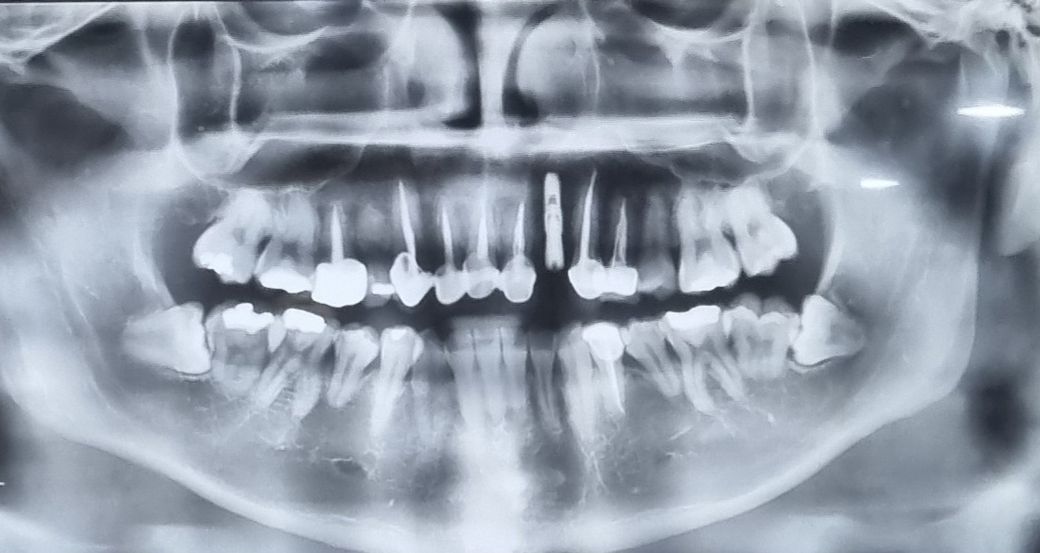

치아 상태 더 나아질려면 어떻게 해야할까요?

20대인데 아직 관리를 못받아서 ㅠㅠ 크라운이랑 임플란트 있습니다. 어떻게 앞으로 관리해야 치아를 더 오래오래 쓸수 있을까요? 치아보험은 무조건 비싼거 들어야겠죠?

• 1번 째 사진